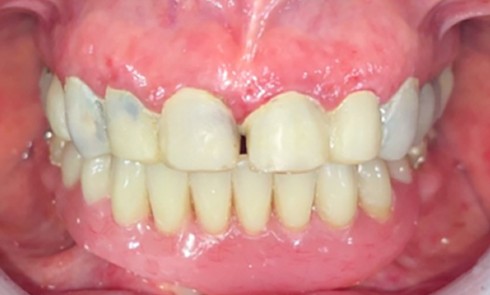

D’autres anomalies dentaires peuvent également être retrouvées chez les patients atteints : des anomalies de taille (microdontie) ou de forme (dents coniques) [1, 6]. Parmi les anomalies orales observées, on peut noter un défaut d’éruption des dents, une persistance des dents temporaires parfois associée à une infraclusion de ces dernières, et la présence de diastèmes [7]. De plus, de manière similaire à la résorption osseuse observée à la suite d’une avulsion dentaire, les dimensions osseuses chez le patient oligodonte sont souvent réduites [8].